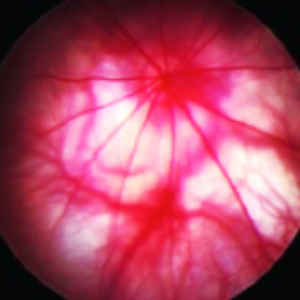

CBI provides special techniques including, OCT (See our OCT video), ERG, ocular ultrasound, gonioscopy, tonometry, laser photocoagulation, slit lamp, funduscopy, pachymetry, Schirmer test, phenol red thread test, hypoxic or hyperoxic chambers, retinal angiography, device implantation, lens removal or insertion, whole mount preparation, ocular histology and immunohistochemistry and ocular photography.

- Funduscopy and Angiography